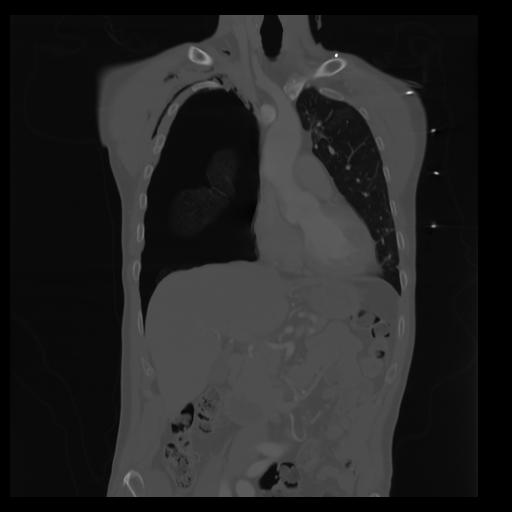

29 CUERPO,CE,Coronal,3.000,CUERPO,Coronal,